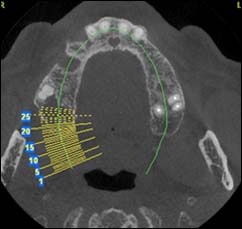

EXAMENS TOMOGRAPHIES VOLUMIQUES TYPE SCANNER OU CÔNE BEAM :

Dernière technologie à notre disposition, cette technique permet de voir en 3 dimensions des images de votre bouche et de mettre en évidence des pathologies ou des anomalies que les autres techniques ne permettent pas d’objectiver.

Reconstruction coronale